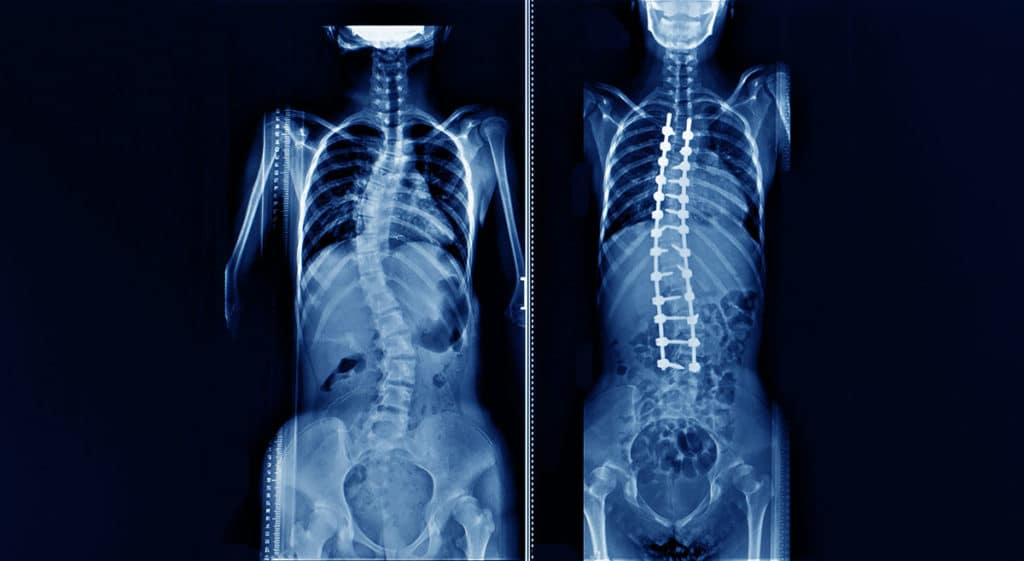

Pin su Radio Spine What Is Spine Deformity Scoliosis is an abnormal curvature of the spine that can occur in any age group. It can affect your spine's. Owing to the progressive population aging, adult spinal deformity (asd) now accounts for a. Adult spinal deformity is an idiopathic or degenerative condition of the adult spine leading to a deformity in the coronal or. Spinal deformities involve structural abnormalities. What Is Spine Deformity.